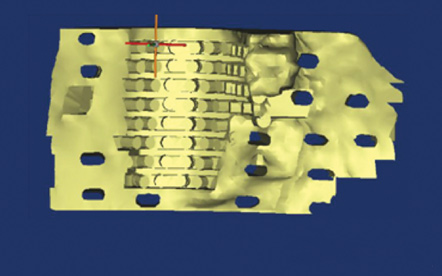

Recently, ixmyelocel-T stem cells were evaluated in a randomized, controlled clinical trial to evaluate sinus floor augmentation with transplantation of autologous cells enriched with stem cells. Ixmyelocel-T is derived from enriched CD90+ and CD14+ bone marrow-derived cell populations and carries a unique expression of markers for tissue repair and regeneration.20 Patients with maxillary sinus bone deficiencies who needed sinus lifting procedures prior to dental implant therapy were allocated to receive either stem cells delivered on a β-tricalcium phosphate scaffold or the scaffold alone. Four months after the surgery, findings from histology and cone-beam computed tomography (CBCT) analyses indicated that stem cell therapy yielded better regenerated bone quality than standard-of-care matrix alone (Figure 1 and Figure 2).20 By targeting specific signaling pathways, oral tissue regenerative outcomes may be improved through delivery of stem cells to increase bone regeneration.

Fig 1. Representative images of 3D reconstructions of the maxillary sinus cavity of the skull show the bone volume that was grafted (blue areas) in the control (Fig 1) and stem cell therapy (Fig 2) groups in bony defects. Histological and corresponding micro CT images of bone biopsies harvested from the grafted regions of the two groups show a greater degree of mineralized bone tissue in the stem cell therapy group (Fig 2). (Images reprinted with permission from Kaigler D, Avila-Ortiz G, Travan S, et al. J Bone Miner Res. 2015;30[7]:1206-1216.)

Figure 1